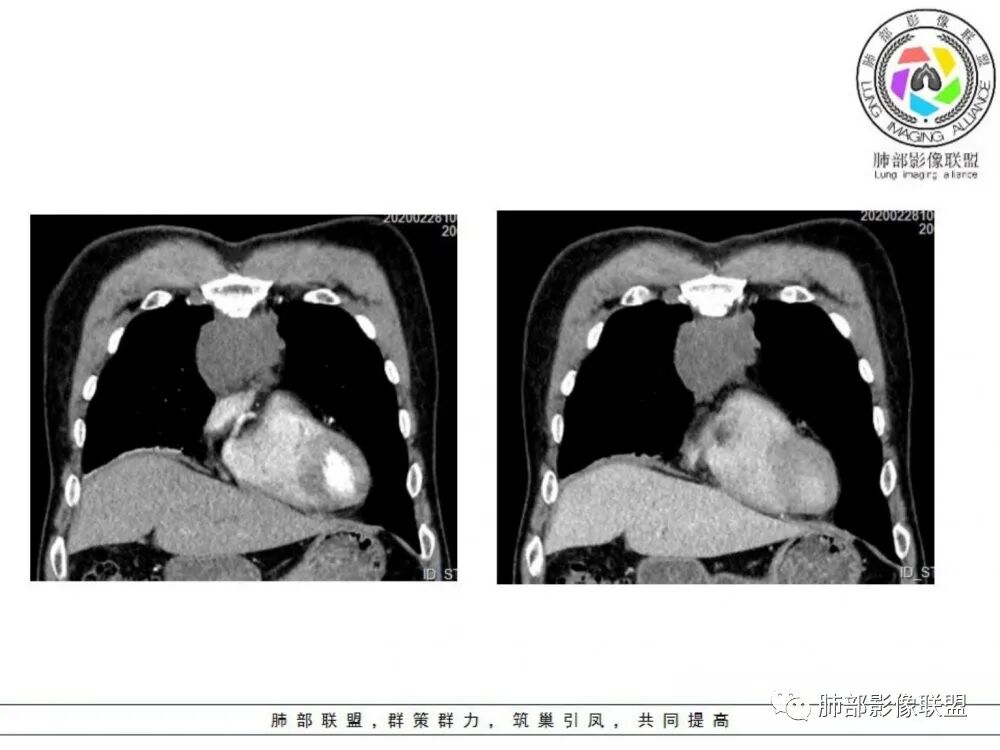

男性患者,65岁,前胸后背疼痛一个月。影像学前上纵隔分叶状的软组织肿块,肿块形态怪异,偏软,位于大血管间隙前,并有向血管后间隙发展的趋势,平扫CT值为40左右,增强扫描中心部未见强化,周围轻度的强化,约为50左右。前上纵隔的疾病谱包抬胸廓内甲状腺肿、胸腺瘤/癌、畸胎瘤、淋巴瘤。少见的心包囊肿或支气管囊肿。根据肿块的形态及强化特点,首先还是排除了胸内甲状腺肿及胸腺来源的肿物,这类的肿物强化比较明显。畸胎瘤成分比较复杂,具有软组织钙化或者脂肪类的组织,这个肿物虽然在平扫的时候好像有斑点状的钙化灶,但是总体成分还是比较单一,所以还是排除畸胎瘤的诊断。所以这样的情况是考虑:淋巴类的肿瘤,注意排除心包的囊肿或支气管来源的囊肿。

老年男性患者,前膈软组织肿块,边缘轮廓不光整,边界似乎尚清晰,内见小点状钙化灶,平扫密度欠均匀,增强后轻度强化表现,边缘有些斑片状的高强化区。综合考虑胸腺瘤或胸腺鳞癌,神经内分泌癌强化弱了一些。患者年龄较大,生殖细胞肿瘤不考虑,淋巴瘤血管包绕不够,可能性不大

老年男性,前胸后背痛一个月,前纵隔不规则肿块,分叶,向纵隔血管间隙进入,且与纵隔血管分界不清,增强边缘轻度强化,中间可见无强化区,似见点状钙化,PET为高代谢,考虑为来源于胸腺,胸腺瘤或胸腺鳞癌可能

临床,老年男性,病史一月。1 定位,骑跨大血管,大部分位于胸腺区域内,周边部分胸腺脂肪有混浑浊,起源于胸腺区的组织应该没有问题。2 定性 。恶性征像,分叶,大血管侵润,pet高代谢,左侧庄层胸膜增厚(类似脑膜瘤的脑膜尾征,良性表现?)。良性征像,病灶均匀,无明确坏死?综合恶性征像多些,考虑恶性可能大。病灶分两部分,部分层面似有明确分割,两个性质的病灶长一块,还是,一个病灶两种不同成分?一个病灶伴均匀坏死?CT值41hu,坏死好像高了点,一个病灶,相同成分,只是血管分布不同,增强是持续流入型强化。纤维类?编不下去了,岔路太多,祭出法宝按概率蒙吧:侵袭性胸腺瘤>神经纤维瘤>乏血供CD

中老年男性,前纵隔占位,基本居中,向两侧生长;边缘膨隆分叶,部分边界不清,增强不均匀轻中度强化,坏死区边界不清;周围多发增大淋巴结,考虑恶性。主要在胸腺癌、胸腺瘤、淋巴瘤之间鉴别。病灶偏软,有钻缝样生长,这些征象偏向于淋巴瘤。但此例老年患者,病灶内有点状钙化,缺乏结节堆砌感,倾向胸腺癌诊断。